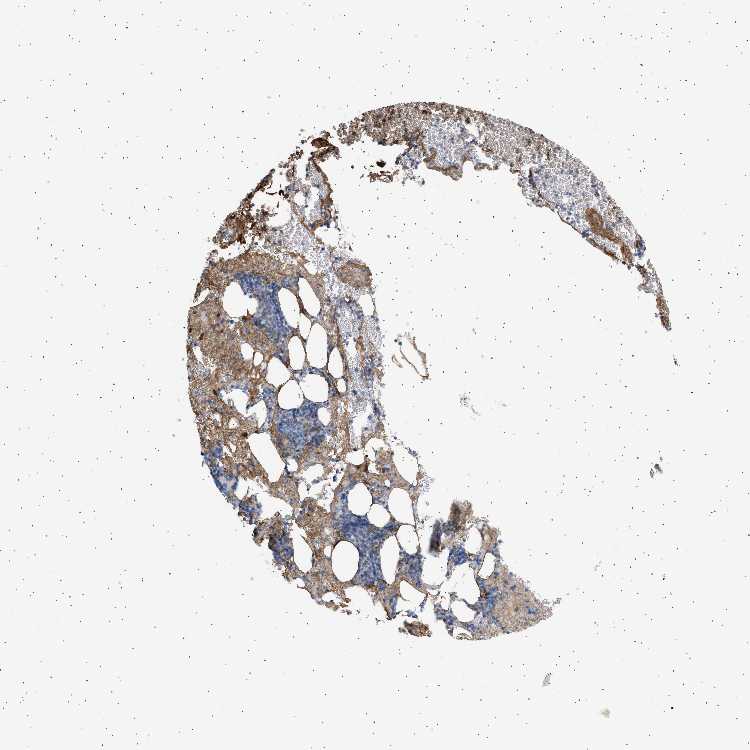

BONE MARROW - Antibody stainingi

Antibody staining in the annotated cell types in the current human tissue is reported as not detected, low, medium, or high, based on conventional immunohistochemistry profiling in selected tissues. This score is based on the combination of the staining intensity and fraction of stained cells.

Each image is clickable and will lead to virtual microscopy that enables deeper exploration of all samples and also displays staining intensity scores, fraction scores and subcellular localization as well as patient and tissue information for each sample.

Antibody HPA060604Antibody CAB016072

Hematopoietic cells Not detectedMedium